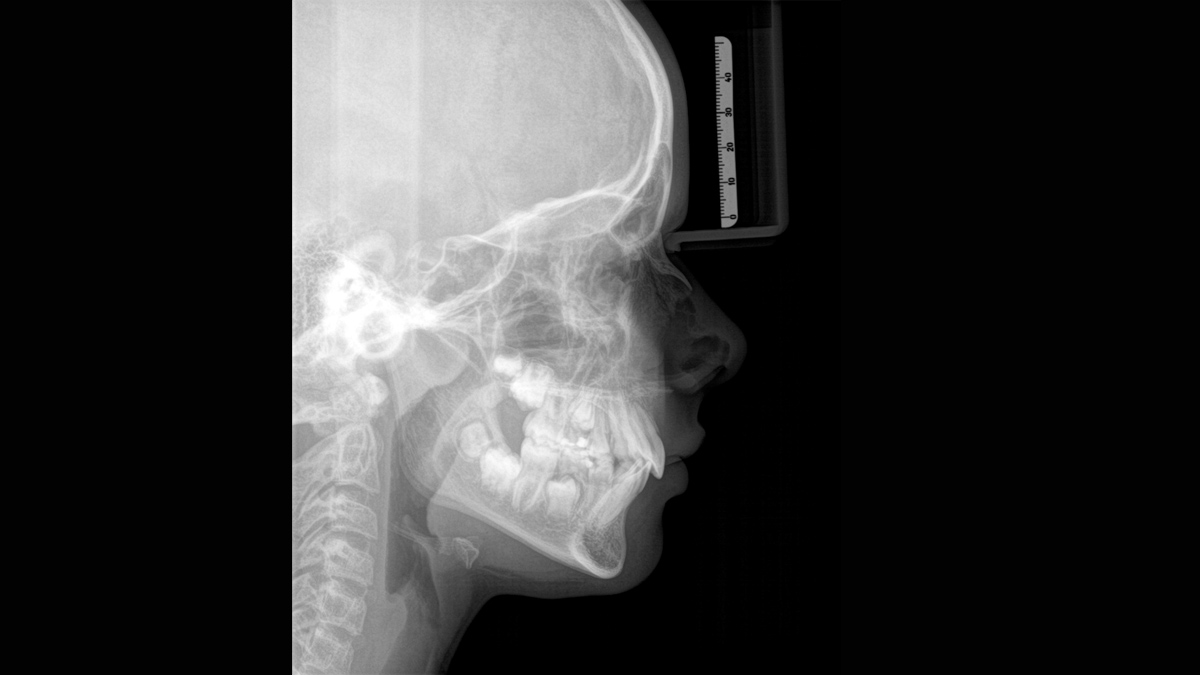

Imagen cefalométrica

Orthophos SL 3D ofrece la posibilidad de instalar un brazo cefalométrico en cualquier momento. Para asegurarse de que se ajusta a su sala de rayos X, el brazo puede montarse en el lado derecho o el lado izquierdo de la unidad.

Programas cefalométricos que cubren todas las necesidades ortodóncicas

Usando un sensor específico, obtiene imágenes laterales y simétricas, así como imágenes del carpo. En casos de dientes desplazados, podría recurrrir a los beneficios de las radiografías en 3D para determinar la localización exacta.